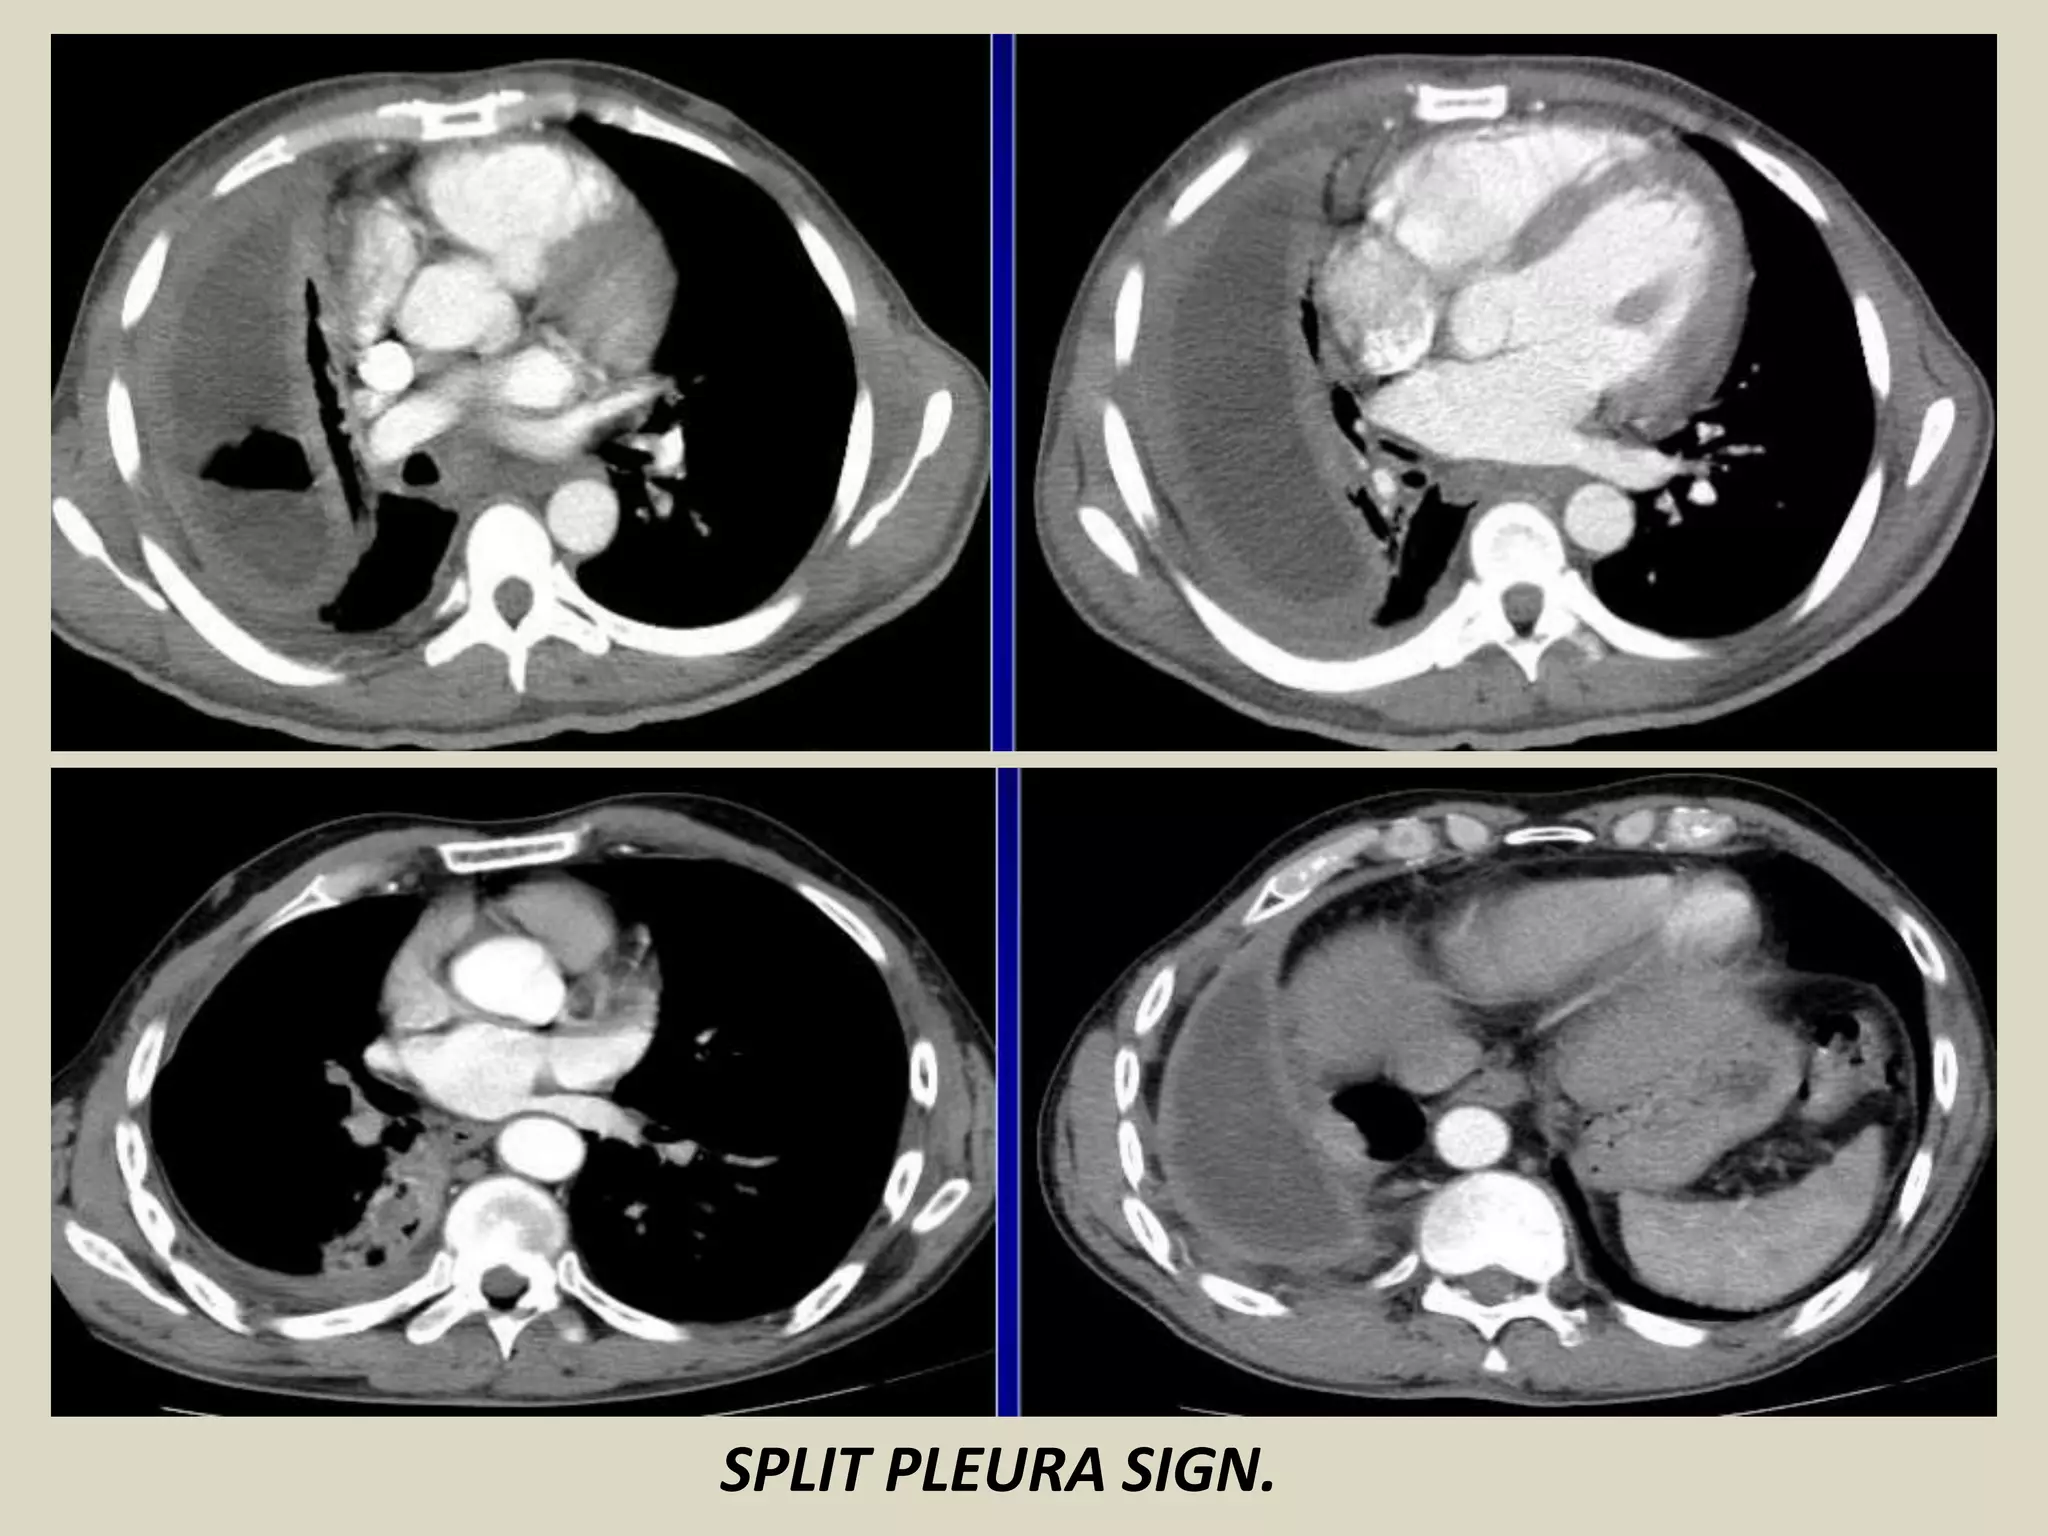

SPLIT PLEURA SIGN

Seen on contrast enhanced CT of chest

Separation and enhancement of the visceral and parietal

pleural layers on CT is considered strong evidence of empyema

Normally, individual pleural layers are not discernable as

discrete structures

Empyemic fluid fills the pleural space, resulting in thickening

and enhancement of the pleura with a denotable separation

It can also be seen with exudative effusion

Causes:

- bacterial pneumonia

- cancer

- viral infection

- PE

SPLIT PLEURA SIGN. Chest radiograph with schematic drawing.

SPLIT PLEURA SIGN.